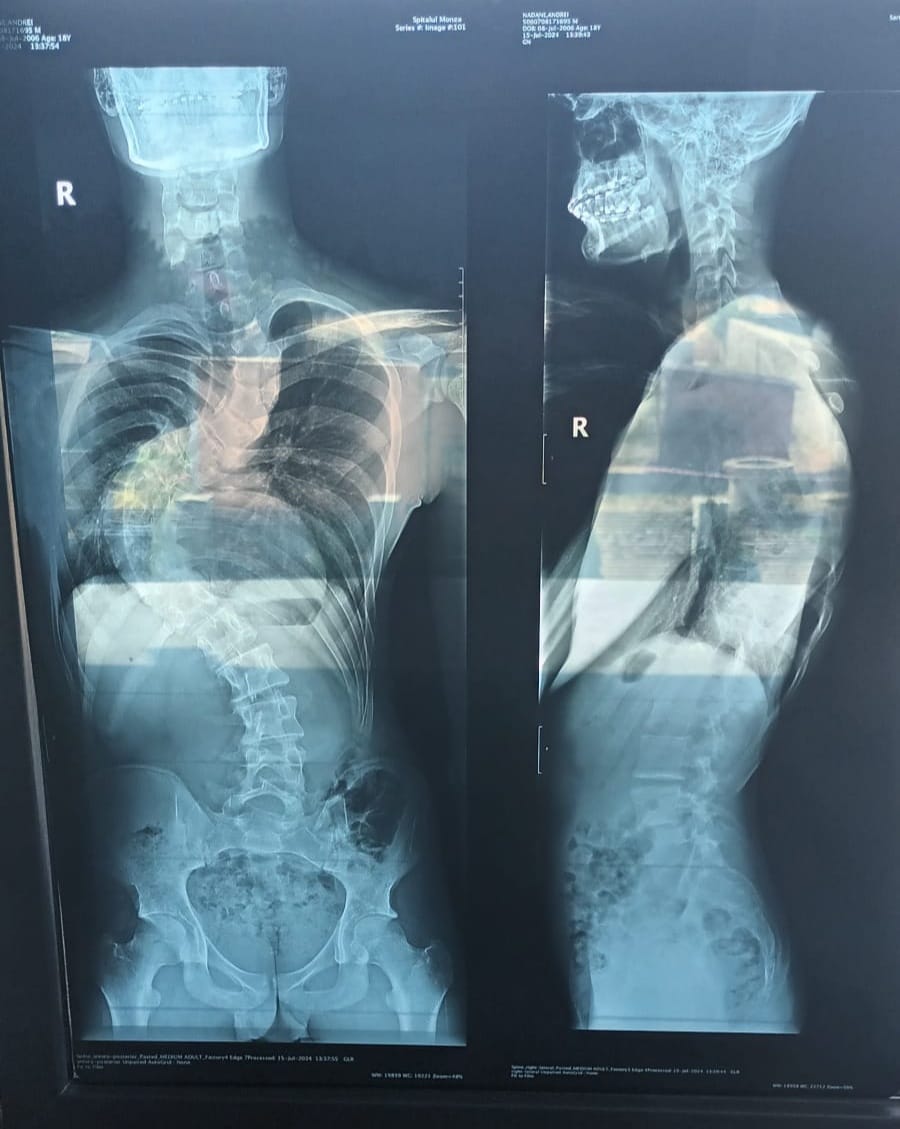

Un cavaler plin de speranțe și cu un viitor înainte suferă de Scolioză T7-T12.

Din păcate toate tratamentele și terapiile au fost fără succes

Însă la București șansele sunt mai mari și poate fi operat la Spitalul Monza.